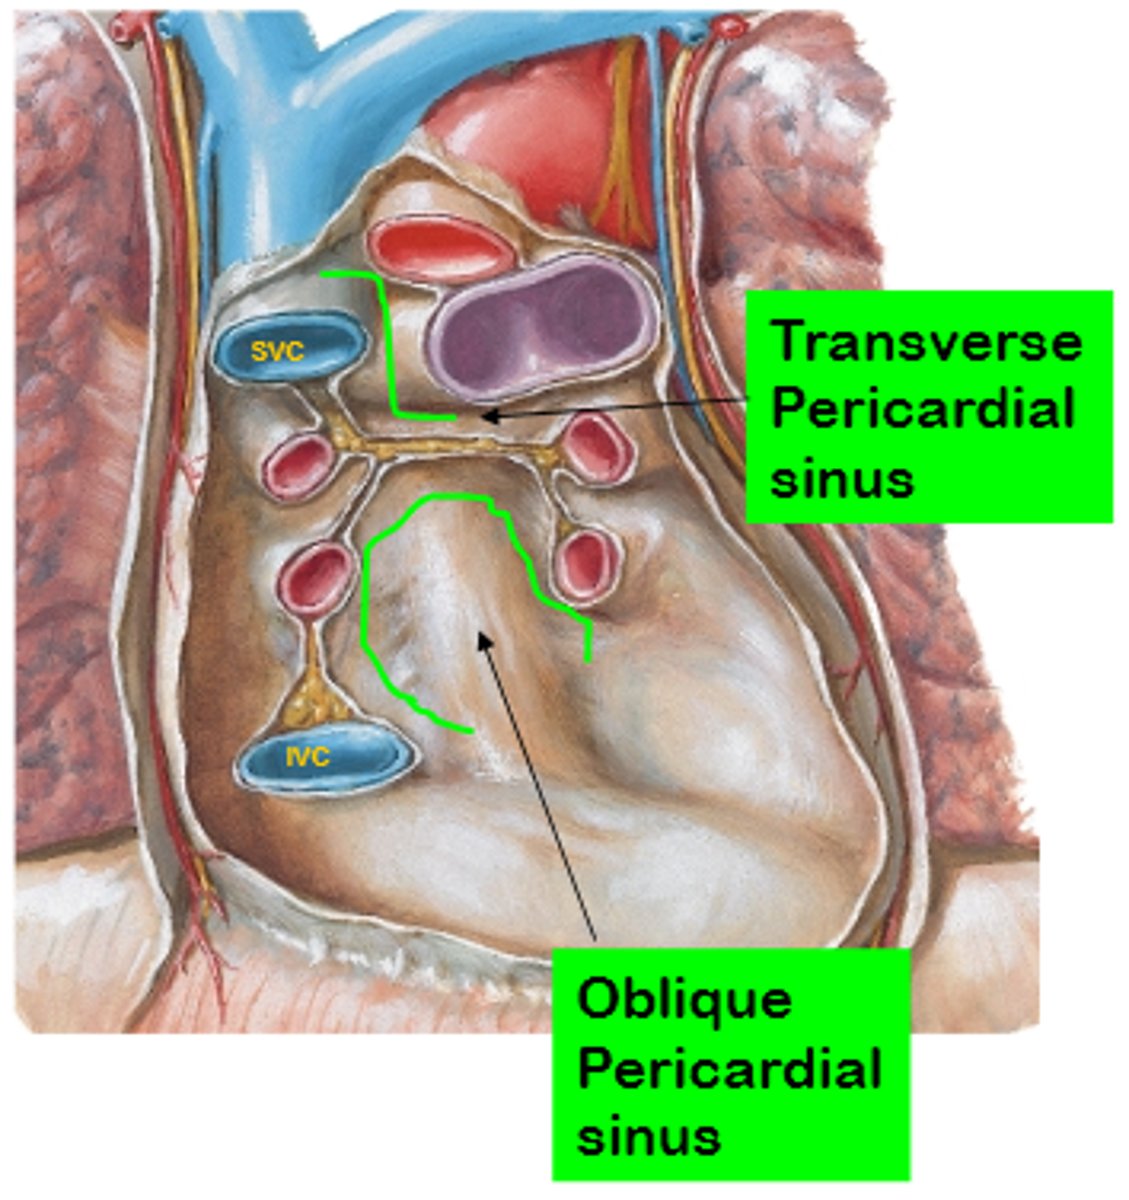

What are the pericardial sinuses and their relevance?

. transverse sinus

. oblique sinus

. Allow for the passage of structures such as blood vessels

. Clinically significant as potential sites of fluid accumulation.

What is the transverse sinus of the pericardium ?

. space posterior to the aorta and pulmonary trunk

. anterior to vena cava

EMBRIOLOGICALLY COMES FROM THE DISINTEGRATION OF THE DORSAL MESOCARDIUM

Clinical significance of the transverse sinus?

Surgeons use it during cardiac procedures.

By passing a finger or clamp through the sinus they can isolate these arteries and control blood flow to the heart during surgeries like coronary artery bypass grafting (CABG).

What is the oblique sinus of the pericardium?

Area where the parietal pericardium reflects (transition) into the visceral pericardium.

Posterior to the heart, cradled by the left atrium and the pulmonary veins.